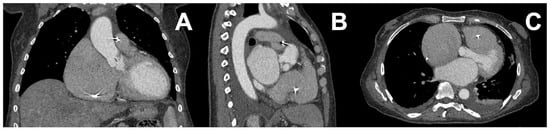

- Bertolini, M.; Rossoni, M.; Colombo, G. Operative Workflow from CT to 3D Printing of the Heart: Opportunities and Challenges. Bioengineering 2021, 8, 130. [Google Scholar] [CrossRef]

- Abudayyeh, I.; Gordon, B.; Ansari, M.M.; Jutzy, K.; Stoletniy, L.; Hilliard, A. A practical guide to cardiovascular 3D printing in clinical practice: Overview and examples. J. Interv. Cardiol. 2017, 31, 375–383. [Google Scholar] [CrossRef]